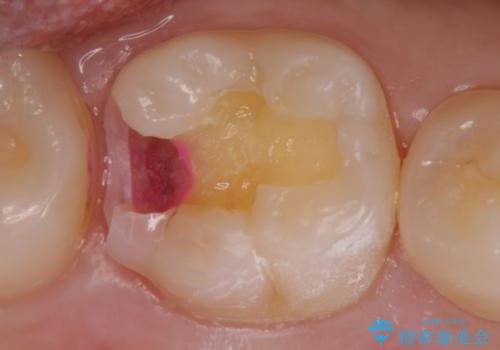

- 検査の結果虫歯が確認された患者様です。

見た目ではわかりにくい虫歯ですが、レントゲン画像でははっきりと写っていました。

まだ虫歯の大きさが小さいためインレーでの修復処置を行います。